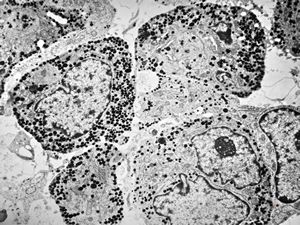

F, 71y. | carcinoid … metastasis to lymphonode